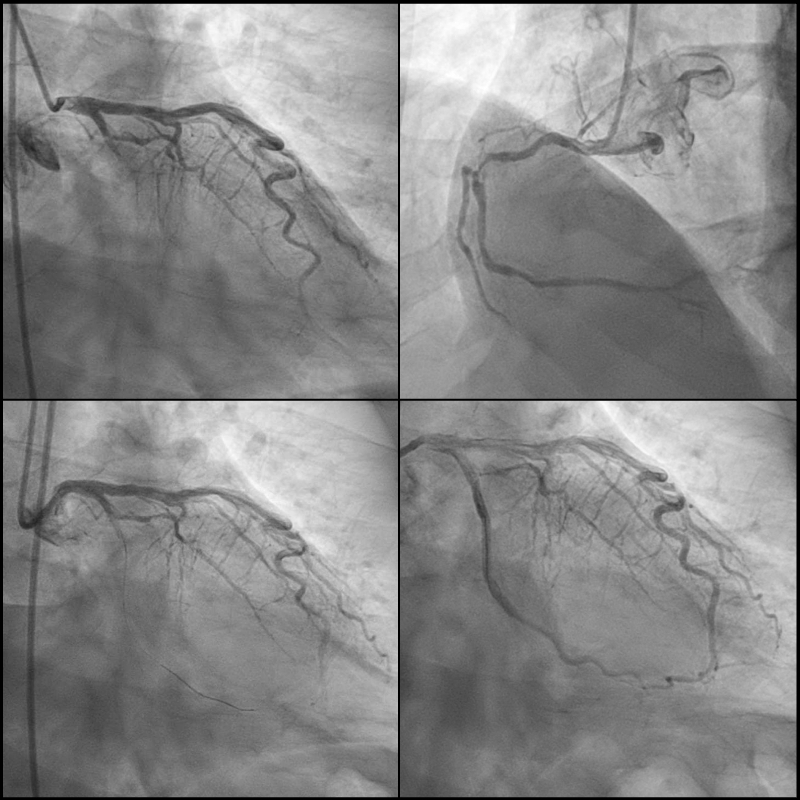

A 60-year-old man with history of hypertension, diabetes, and remote history of unprovoked lower extremity DVT presented with dyspnea for 3 days and chest pain for 1 day. Initial ECG revealed acute inferolateral STEMI (Figure 1A). Initial labs showed marked polycythemia (hemoglobin 21.6 g/dL, hematocrit 65%). Emergent coronary angiogram (CAG) demonstrated 100% occlusion of the LCx (Figure 2), where PCI with 4 drug-eluting stents (DES) was performed. There was residual 85% stenosis of the RCA. Echocardiogram showed ejection fraction (EF) 45% with severe hypokinesis of the inferolateral wall. Patient was started on aspirin, prasugrel, and rosuvastatin. Given his polycythemia and history of DVT, hematology was consulted and started apixaban for secondary thromboprophylaxis with no indication of phlebotomy in the setting of recent STEMI. JAK2 V617F mutation positive confirmed the diagnosis of polycythemia vera (PV). Hospital course was complicated by worsening renal function, likely due to contrast-induced nephropathy and/or cholesterol emboli.

One week later, he developed acute epigastric pain and hypotension requiring vasopressors. Despite triple therapy (aspirin, prasugrel, apixaban), ECG indicated lateral STEMI (Figure 1B). Repeated CAG showed a new thrombus in the proximal LCx stents though there was TIMI 3 flow (Figure 3). Aspiration thrombectomy with 2 additional DES were placed. Right heart catheterization revealed mixed cardiogenic and vasoplegic shock, most likely from metabolic acidosis and uremia. A temporary ventricular support device was inserted, and CRRT was started. Repeated echocardiogram showed EF 30%. Patient subsequently developed DIC and multiorgan failure. Despite maximal support, he developed coffee ground emesis which was likely aspirated leading to PEA cardiac arrest.